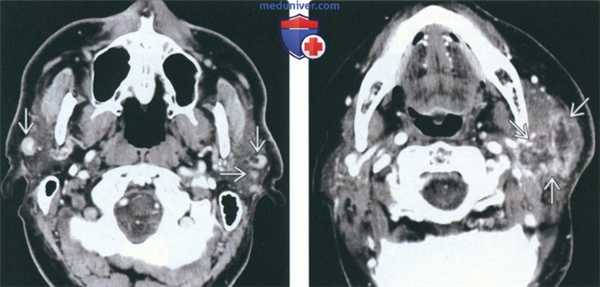

(Слева) На аксиальной КТ с КУ визуализируется сливная опухоль, замещающая хвост околоушной железы. Определяется также распространенная метастатическая лимфаденопатия I и II уровня. У пациента-плоскоклеточный рак кожи наружных отделов волосистой части головы.

(Справа) На аксиальной КТ с КУ определяется агрессивный первичный плоскоклеточный рак кожи с распространением в глубокие подкожные мягкие ткани. Обратите внимание на поражение лимфоузла первой очереди в хвосте околоушной железы.

(Слева) На аксиальной КТ с КУ визуализируются контрастирующиеся опухоли в обеих околоушных железах - системные ме тастазы на фоне лимфолейкоза в сочетании с распространенной шейной лимфаденопатией (не показана).

(Справа) На аксиальной КТ с КУ в левой околоушной железе визуализируется неравномерно контрастирующаяся опухоль с нечеткими границами. Центральный некроз и нечеткие границы - признаки экстра-капсулярного распространения. Опухоль околоушной железы -регионарный метастаз ангиосаркомы волосистой части головы.